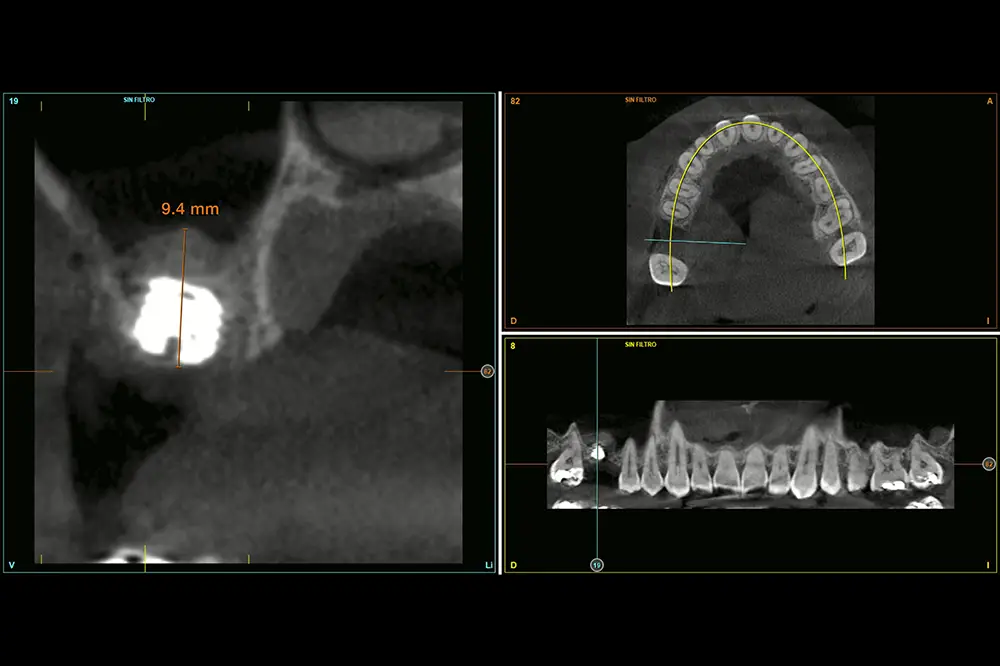

Procedemos a la extracción de la pieza dental y regeneración con PRGF-Endoret, además de un legrado minucioso de la lesión periapical para lograr una mejor regeneración del alveolo dental. Cuatro meses después de la extracción y regeneración del alveolo, se realiza un nuevo TAC de control para constatar la altura ósea residual y planificar la cirugía del implante. En la medición de la altura en la zona de inserción del implante podemos observar como existe únicamente 1,5 mm a nivel de la zona más vestibular de la cresta y de 3 mm en la zona palatina. Esto nos hace planificar un implante de 4,5 mm de altura (fig. 3) en esta posición, anclado sobre todo en la zona más palatina (anclaje vestíbulo-palatino), que nos permitirá realizar un abordaje crestal del seno con hueso autólogo como material de injerto, utilizando el implante como implante transicional que va a impedir el colapso del injerto primario (fig. 4).

Fig. 3. Medición en el TAC de planificación de la altura del tramo edéntulo para planificar el implante a insertar. Podemos ver cómo en la zona más vestibular únicamente disponemos de 1,5 mm y en la zona más palatina de 3 mm. Esto nos permitirá anclar el implante.